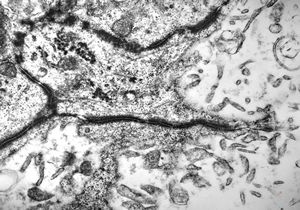

F,49y. | purulent meningitis- meningococcal v.s.

F,49y. | purulent meningitis- meningococcal v.s.

F,49y. | purulent meningitis- meningococcal v.s.